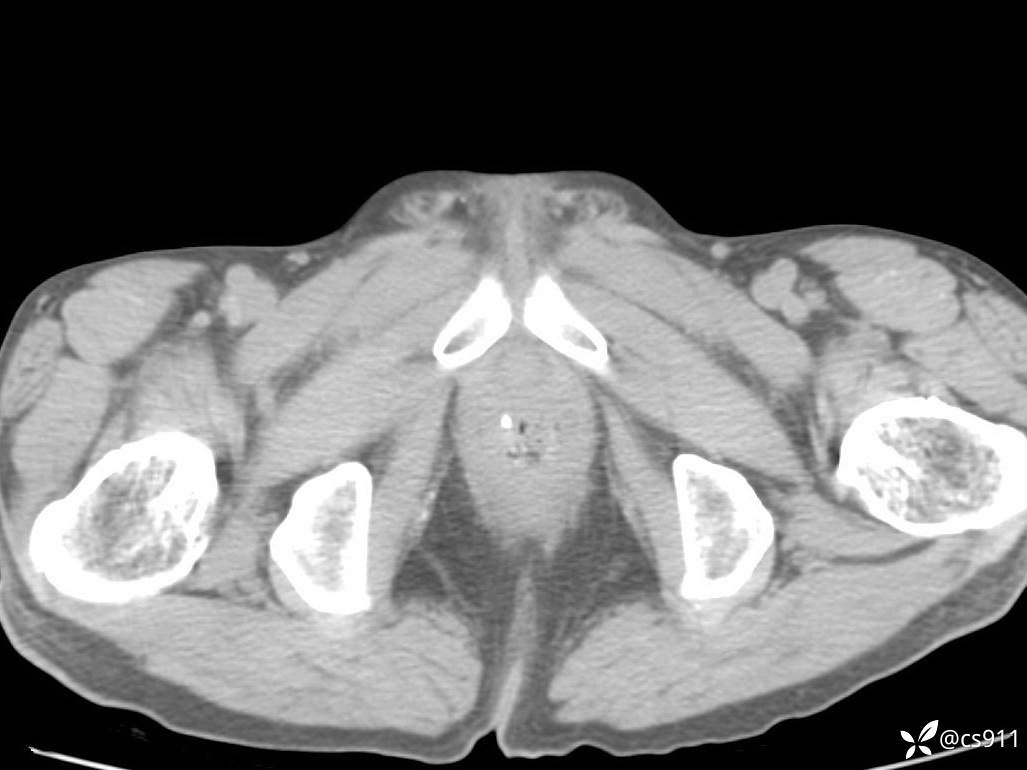

急腹症之急诊CT,原因?答案公布

男,77岁,腹痛、腹胀伴恶心呕吐1天。呕吐胃内容物,非喷射性呕吐,有咖啡色样胃内容物,诉有胃穿孔病史。查体:全腹平,下腹部压痛,全腹无反跳痛,叩诊呈浊音,移动性浊音阴性,肠鸣音减弱,1-2次/分。肛检:直肠未扪及明显肿物,可触及大量粪块。

血淀粉酶(AMY) HH 1859 U/L 35-135